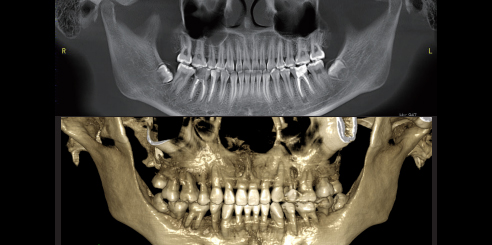

IA + PAN

Reconstrucción panorámica por TC: con el nuevo algoritmo de reconstrucción por TC basado en aprendizaje profundo, el sistema puede obtener una imagen CBCT precisa. Imágenes panorámicas: Junto con el nuevo enfoque automático inteligente y la tecnología panorámica multicapa, el sistema ajusta automáticamente las mejores curvas panorámicas y reconstruye una mejor imagen.